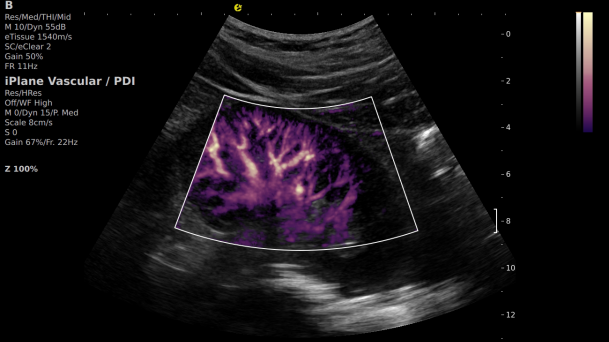

1) 基于OmniSound?平面波超快速平台,超声信号采集帧频提高了200倍(25000Hz)。

2) 可检测20-50μm级细小血管低速血流信号,能看清头发丝1/2粗细的微血管;

3) 通过血管指数(VI)定量评估局部血管密度,以定量化数据实时监测血流灌注情况,预判肾功能恢复情况;

微米级超高分辨率血流信号显像

超微视血流显像评估肾移植术后灌注情况